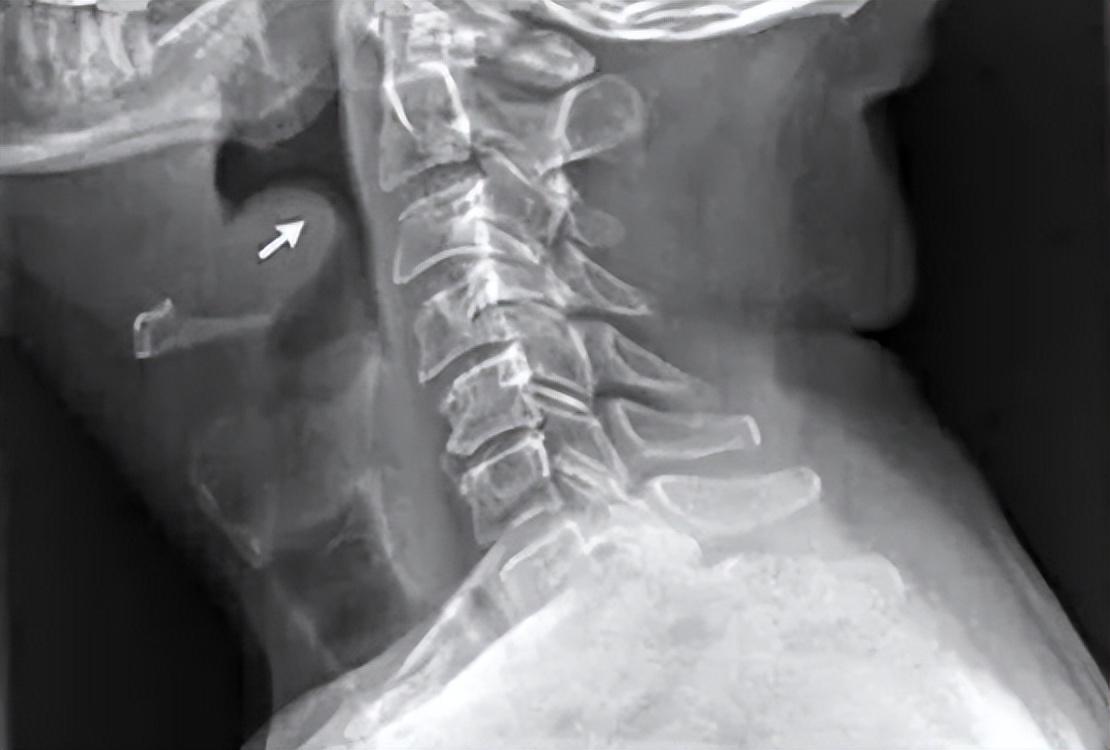

因為病人在入院前就有明顯的咽喉部疼痛,後來癥狀加重出現了吞咽困難,再後來呼吸困難,甚至還出現了憋氣感,還伴隨著畏寒癥狀,這一切都指向了無比兇險的急性會厭炎。加上後來檢查時,患者的會厭腫大明顯,喉嚨呈拇指征,更加肯定了這種猜想。